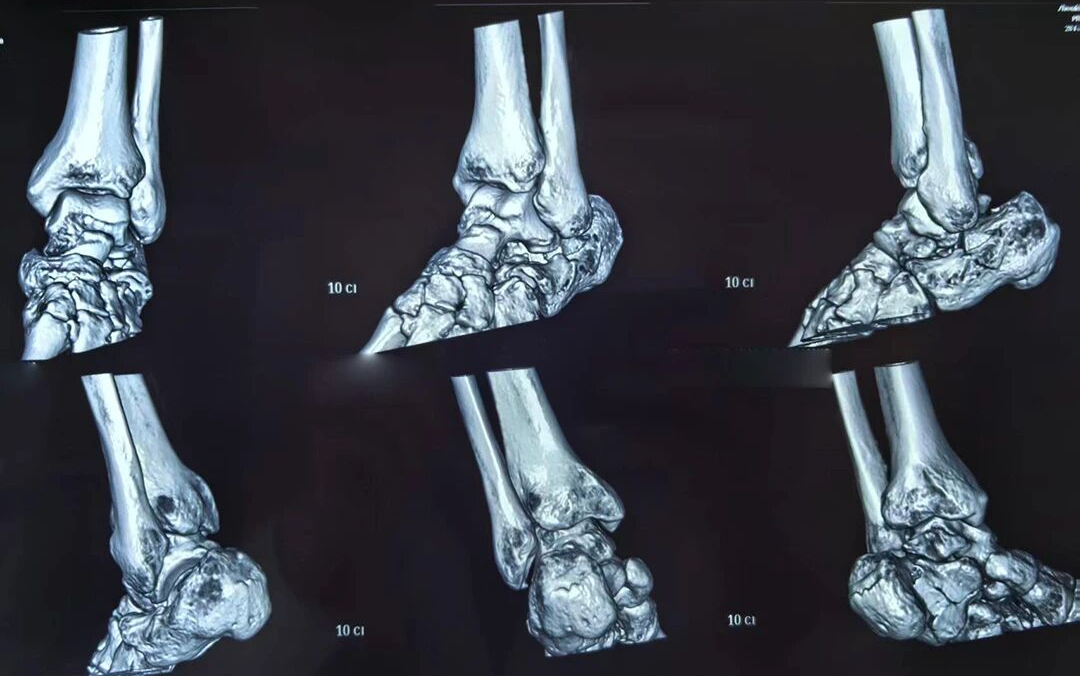

术后

日前,一名高处坠落伤致左侧跟骨粉碎性骨折的患者入院。骨三科团队经充分术前讨论,为其量身定制微创手术方案。术中在X光精准引导下,经皮撬拨复位骨折块,以空心螺钉稳固固定,出血极少、创伤小。术后患者恢复良好,早期即可开展功能锻炼,避免了传统大切口带来的并发症隐患。